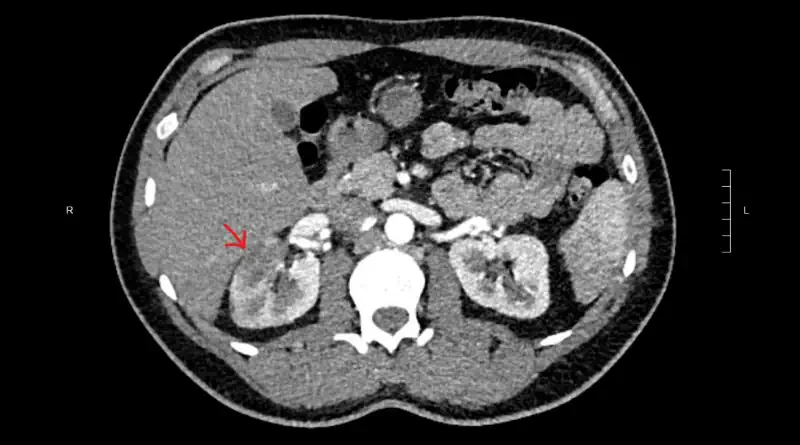

artery blood clot

CT angiogram showing a renal infarction in the right kidney. The cause is a blocked kidney artery.